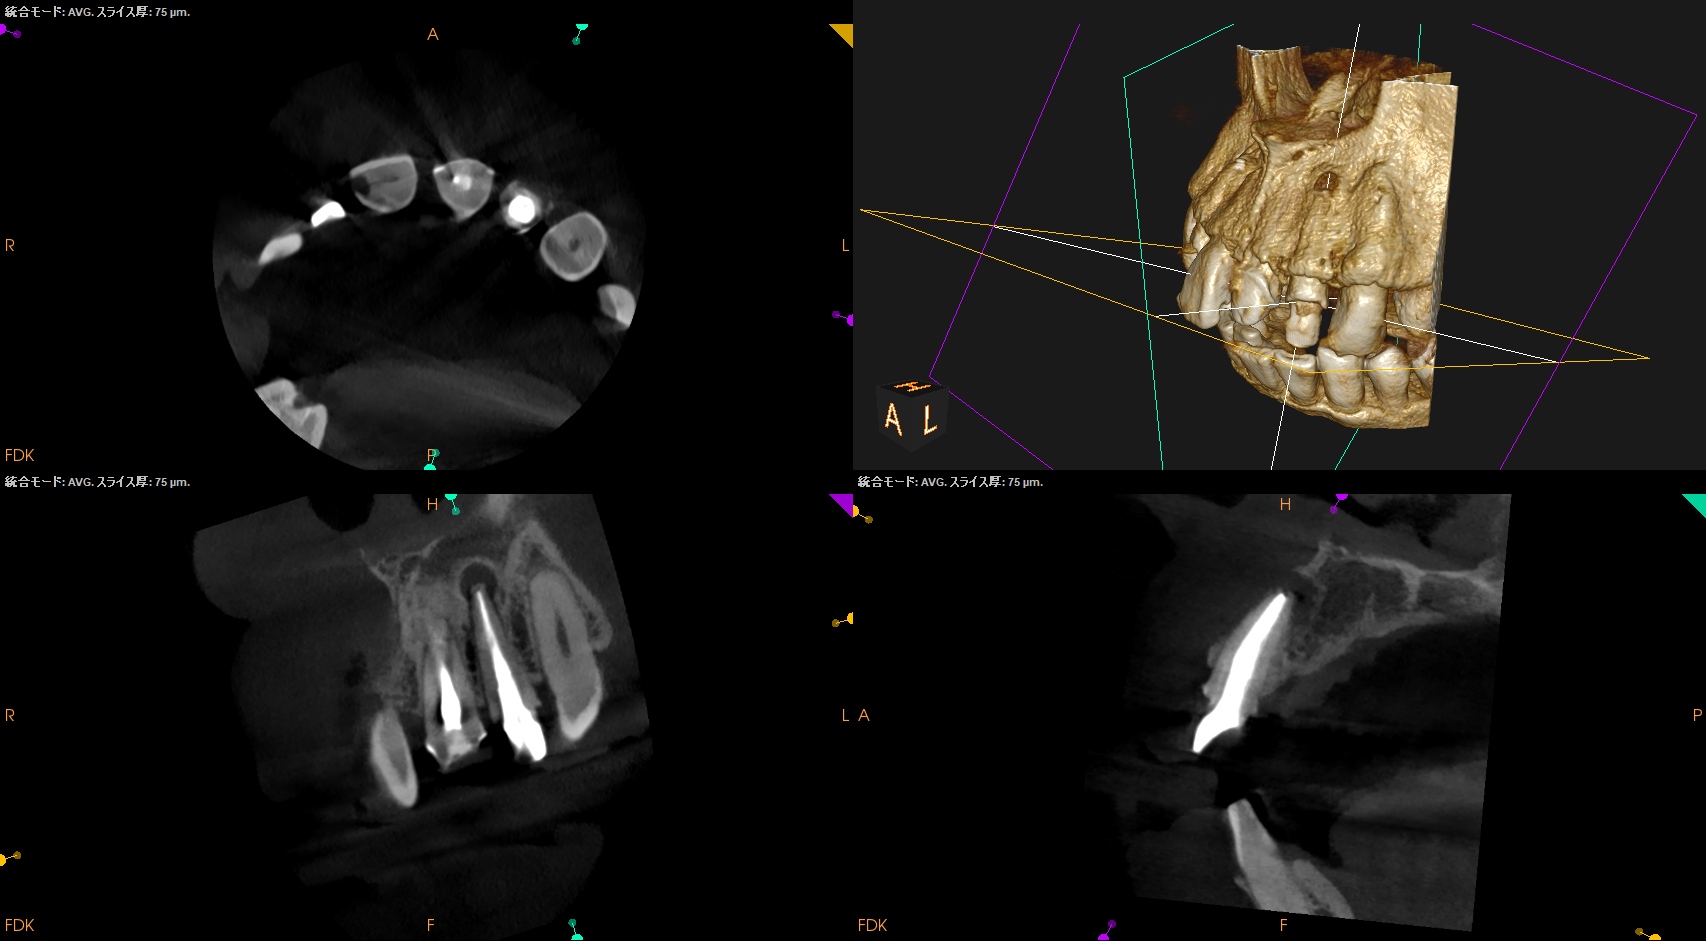

ここから9ヶ月が経過し、かかりつけ医の先生からCBCTを評価してほしいとの依頼があった。

その結果が以下である。

#7

#10

さてこの画像からあなたは治癒傾向であるか否か?を判断できるであろうか?

そう。

よくわからないのである。

なので、実際に当歯科医院で検査も含めて評価することになった。

これでも判然としかねる。